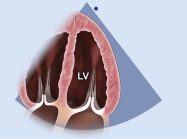

| 2.15. Mặt cắt 4 buồng từ mỏm phóng đại hình ảnh thất trái |

||||||||

|

|

Cửa sổ siêu âm từ mỏm tim

Mặt cắt 4 buồng Điều chỉnh depth để khu trú vào hình ảnh thất trái |

Thất trái (LV) | |||||